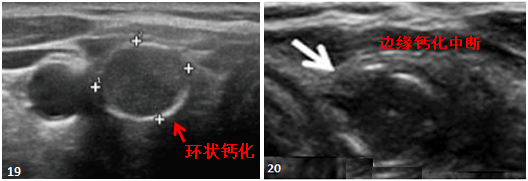

“周围钙化”是指肿瘤边缘的钙化,根据覆盖范围可分为弓形钙化和环形钙化(图19)。 环状钙化中断,提示肿瘤突破并向外浸润,应注意恶变的可能(图20)。

![图片[11]-一份甲状腺超声报告到手,从哪看起?-首码网-网上创业赚钱首码项目发布推广平台](https://mmbiz.qpic.cn/mmbiz_png/XsibUvKtQsKyibvUiaI0WiaTnGBzic2SSvxXQKMAF3QHUxXT6lT9HKjW9vtXDseg20iahD9QlB05gT9ic43uo6JVwtNfg/640?wx_fmt.png)

图 19:“2016 AACE/ACE/AME 指南:甲状腺结节的诊断和治疗”

图20:“ATA结节的超声表现和恶变风险”